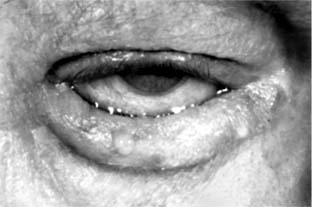

Entropion-turning inward of the lid (Figure 4-3)-may be involutional (spastic, senile), cicatricial, or congenital. Involutional entropion is most common and by definition occurs as a result of aging. It always affects the lower lid and is the result of a combination of laxity of the lower lid retractors, upward migration of the preseptal orbicularis muscle, and buckling of the upper tarsal border.

Figure 4-3

Figure 4-3: Entropion. (Courtesy of M Quickert.)